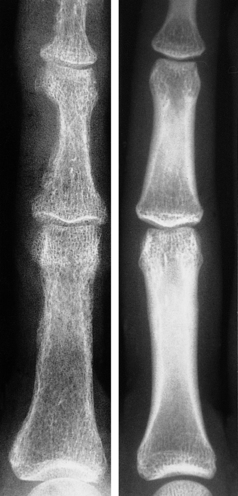

The advanced bone pathology associated with hyperparathyroidism is now rare. In the early stages there are subtle radiological changes such as subperiosteal resorption of phalangeal bone (Fig. 25.7) or characteristic changes around the teeth. As the disease progresses, cystic bone lesions may develop—osteitis fibrosa cystica (von Recklinghausen's disease of bone). These are sometimes referred to as ‘brown tumours’, although they are not neoplasms. The brown appearance is the result of haemorrhage and there is often a marked associated osteoclastic reaction. Because PTH has anabolic as well as catabolic effects in bone, hyperparathyroidism does not usually cause generalised osteoporosis.

image

Fig. 25.7 X-ray of finger in primary hyperparathyroidism (left) and a normal patient (right). The irregular outlines of the phalanges are the result of resorption of bone.